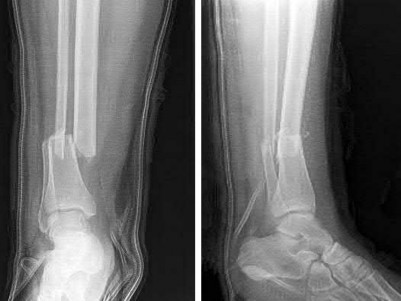

A 28-year-old male sustains a closed comminuted tibial shaft fracture.

Two hours post-injury, he develops severe leg pain unyielding to narcotics. His blood pressure is 120/80 mmHg. Intracompartmental pressure monitoring is performed. Based on current guidelines, which measurement dictates an emergent 4-compartment fasciotomy?

Explanation

Acute compartment syndrome is classically defined by tissue hypoperfusion. The absolute compartment pressure is less reliable than the differential pressure (Delta P). A Delta P (Diastolic Blood Pressure minus Compartment Pressure) of less than 30 mmHg is an absolute indication for emergency fasciotomy, as capillary perfusion gradient is lost when tissue pressure approaches the diastolic pressure.